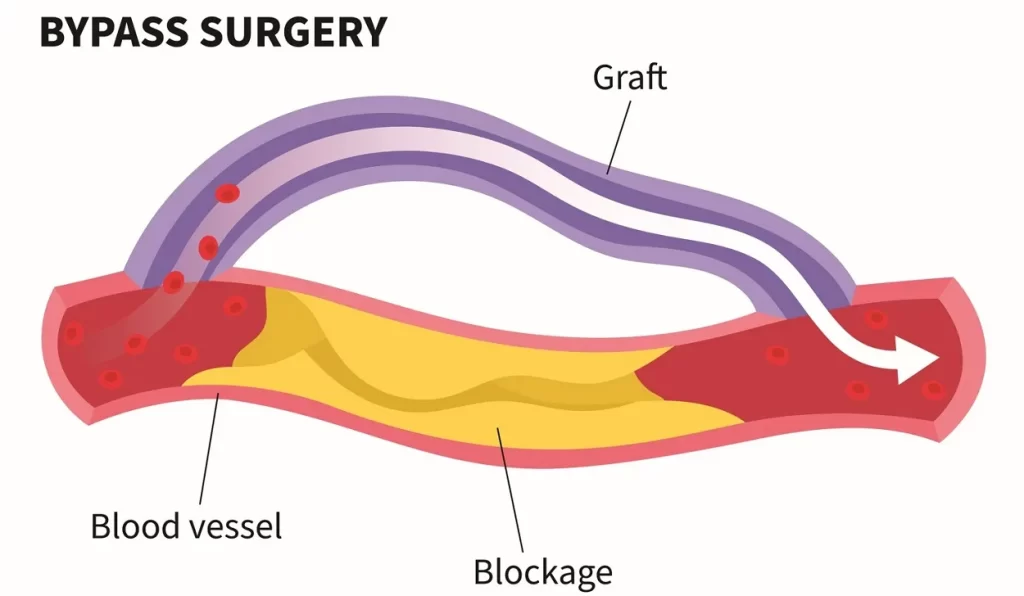

Coronary Artery Bypass Grafting (CABG)

A surgical procedure that improves blood flow to your heart by creating new pathways around blocked coronary arteries.

How it happens: During surgery, your cardiac surgeon takes blood vessels from another part of your body — typically your leg, arm, or chest — and connects them to create detours around blocked portions of your coronary arteries. This reroutes blood flow around the blockage, ensuring your heart muscle receives adequate oxygen and nutrients.

When it’s necessary: We may recommend CABG when you have severe coronary artery disease affecting multiple vessels, or when angioplasty and stenting are not suitable options due to the location or extent of blockages.